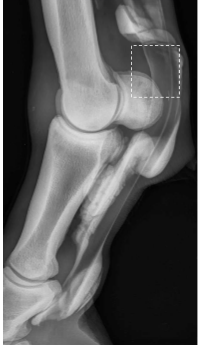

• this horse has thickening on the lateral aspect of the limb in the proximal third of the metacarpus. which soft tissue is involved in this injury?

accessory ligament of the DDFT